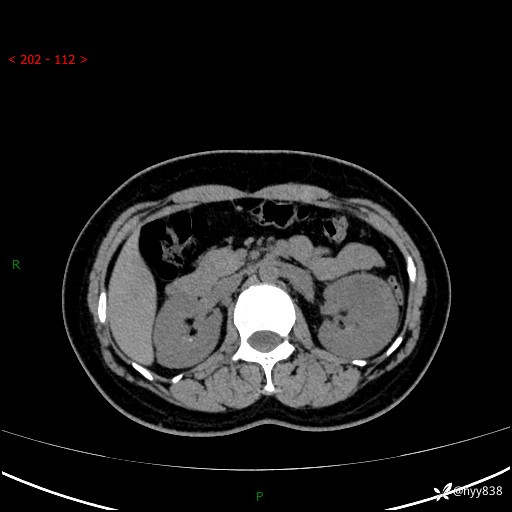

现病史:患者于1周前因左侧腰腹部间断胀痛不适,无恶心呕吐,无明显肉眼血尿,无畏寒发热,无尿频尿急,起病初,患者来我院就诊,查CT提示左肾低密度影,外周血提示:白细胞11.25*10^9/L.行抗感染治疗后未见明显好转,06-18泌尿系增强CT提示左肾类圆形低密度占位(脓肿?肿瘤?),大小:4.0*3.2cm,为求进一步治疗,门诊以“左肾占位”收住我科。 起病以来,患者精神佳,饮食、睡眠良好,大小便正常,体力体重无明显变化。

双肾CT平扫+增强